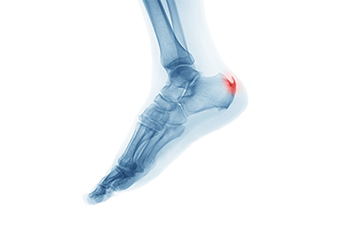

Heel spurs, often associated with persistent heel pain, are bony protrusions that form on the underside of...